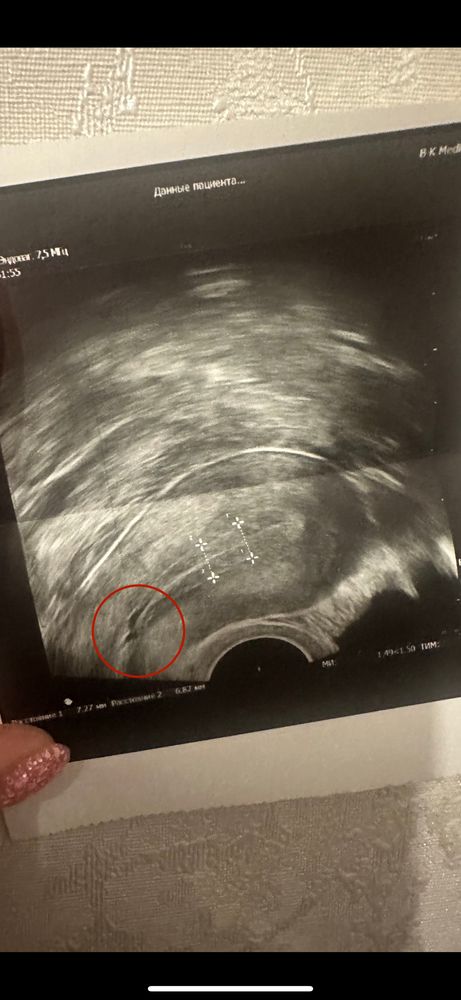

Подскажите по УЗИ

Эндометрий и все о нем (лечение, наращивание, улучшение)Добрый вечер.

что за пятно может быть?Я раньше не замечала.Врач сказала не страшно,но я так не поняла,что это,может сделать 3д узи?На что это вообще похоже?У меня 8го подсадка,я переживаю.